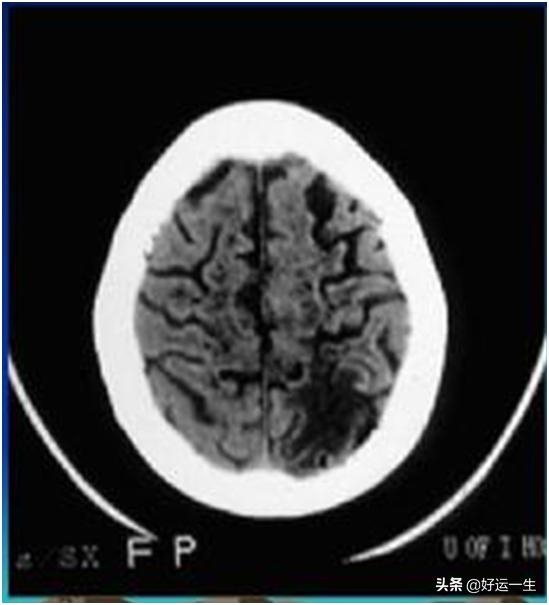

Un infarctus cérébral se présente sous la forme d'une tache noire, appelée médicalement "ombre hypodense". Ces endroits sont les sites des lésions. (Figure 2)